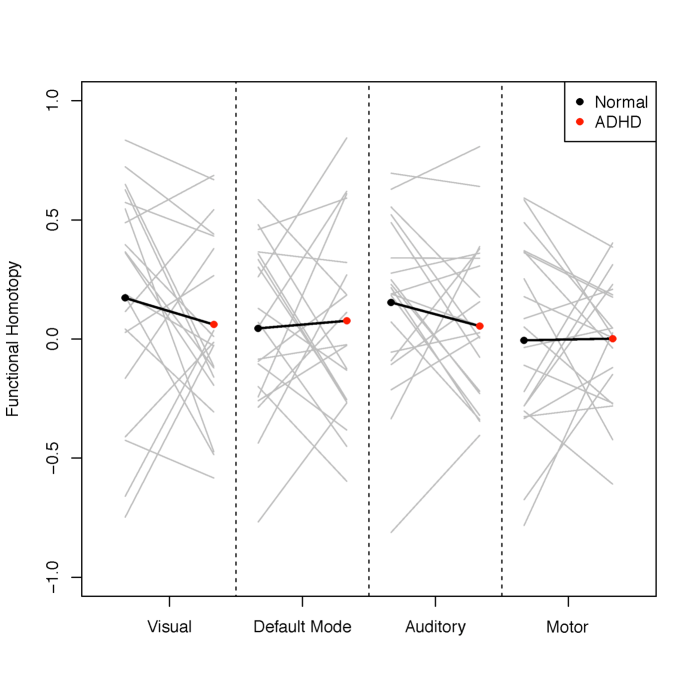

The approach of H-gICA also allows us to calculate the brain functional homotopy of each brain network. To compare the brain functional homotopy of ADHD and typical developed children, we choose 20 ADHD subjects and 20 subject-macthed controls. The subjects and controls were matched in gender and age. Via Equations (4) and (5), the estimated functional homotopy of four networks (visual, default mode, auditory and motor) are shown in Figure 13. As we can see, the functional homotopy of ADHD children tends to be lower in both visual networks and the auditory network. These represent meaningful leads on the exploration of homotopic network relationships and disease, though we leave a full exploration to later work.